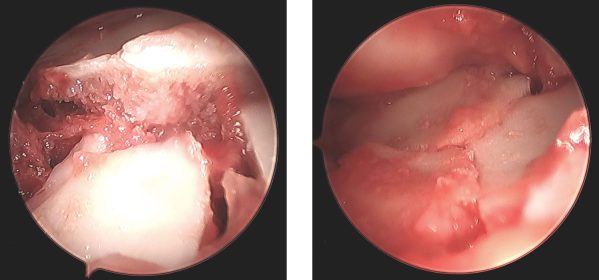

Caso haja envolvimento articular ou outras lesões associadas, pode ser necessário realizar, no mesmo tempo cirúrgico, uma artroscopia do punho, para visualizar o interior da articulação de forma minimamente invasiva.

Imagem da superfície articular antes e após redução assistida por artroscopia

Imagem da superfície articular antes (à esquerda) e após (à direita) redução assistida por artroscopia